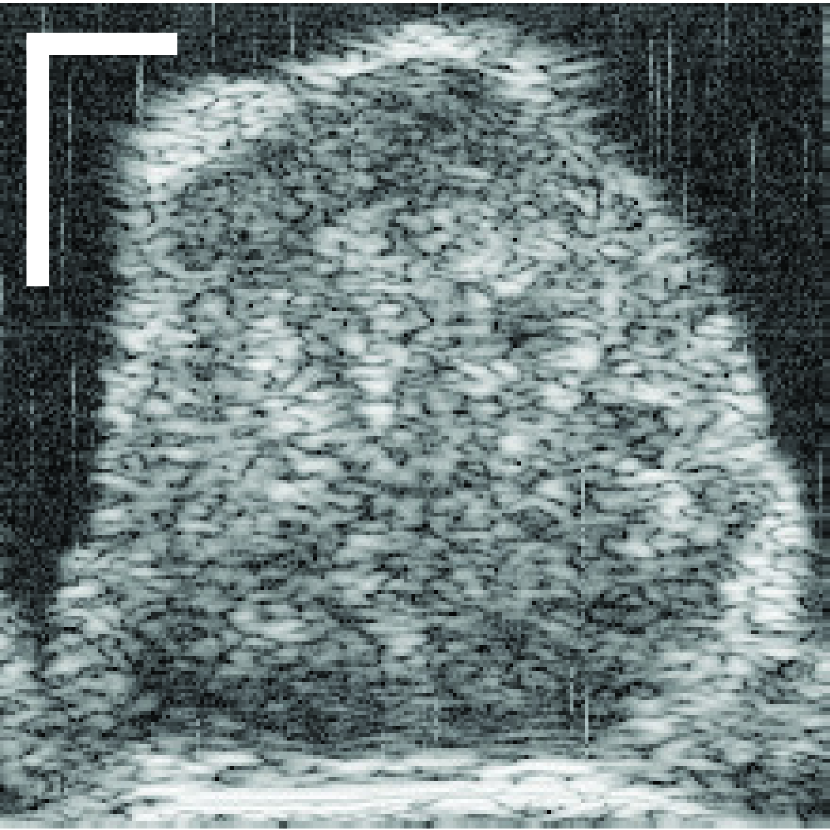

Figure 10: (a) Target HFU image. (b) Manual segmentation result. (c) The result of RFC+STS-LS. (d) The result of NGC with depth-dependent profiles. (e) The result of proposed method without global energy (one round of GC-LAE). (f) The result of proposed method with global energy (two rounds of GC-LAE).

Figure 10 displays the segmentation results of four typical LNs to illustrate the advantages and disadvantages of the three different segmentation methods. RTS-LS with RFC and NGC with depth-dependent profiles segment LNP mainly by intensity information, and GC-LAE-based methods segment LNP mainly by the intensity similarity of local regions.

IV-A1 LNs with Clear Boundary and Consistent Intensity Distributions

The top LN has clear boundary and consistent intensity distributions. Therefore, all four segmentation methods can obtain satisfactory results. However, RFC+STS-LS may converge to a false local minimum during deformation as shown in the top figure of Figure 10(c). In contrast, the GC-based approach can avoid this kind of error.

IV-A2 LNs with Clear Boundary and Non-homogeneous Acoustic Attenuation

As discussed in introduction, depth-dependent profiles may not perform adequately in the presence of inconsistent profiles, where the intensity of voxels within the same depth in one object may not be consistent. To illustrate this point, the second row of Figures 10(c) and 10(d) show the segmentation result of RFC+STS-LS and NGC with depth-dependent profiles, respectively. Comparing these results to the manual-segmentation result in Figure 10(b), we can identify a fat region on the left mislabeled as LNP because the fat in the right region of the image at the same depth is brighter than the fat in left. In this case, NGC with depth-dependent profiles and RFC+STS-LS were unable to correctly segment the fatty region on the left. Because the contrast between LNP and fat is strong enough on the left side of the LN, GC-LAE was able to find the boundary correctly (Figure 10(e) and 10(f)) independent of whether the global-energy term is used.

IV-A3 LNs with Blurry Boundary and Low Intensity Difference between LNP and the Fat

GC-LAE determines a boundary based on the similarity of local intensity distributions. Therefore, it may not be able to find the boundary correctly when the boundary is blurry. In the third LN of Figure 10, the boundary between LNP and the fat in middle is extremely blurry and the intensity difference between them is low. In this case, GC-LAE cannot find the boundary correctly even with global energy because of insufficient contrast, but RFC+STS-LS and NGC with depth-dependent profiles were able to provide better segmentation results according to intensity distributions. RFC+STS-LS obtain the best results in this case by updating intensity distributions gradually with deformation.

IV-A4 LNs with Blurry Boundary and High Intensity Difference between LNP and the Fat

The bottom row in Figure 10 shows a transverse slice of an LN with a “blurry” boundary at the upper left corner, and the intensity of the fat on right is much brighter than LNP. In this case, RFC+STS-LS remained at a false local minimum during the segmentation of this LN. NGC with depth-dependent profiles performed better, but it was adversely influenced by the blurry boundary. GC-LAE without global information also incorrectly segments some bright voxels of LNP as fat. In this example, GC-LAE with a global-energy term has the best performance. Using the additional information provided by the depth-dependent profiles, the resulting boundary nearly matches the true boundary.